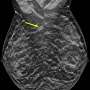

Alarming 24% Rise in Invasive Breast Cancers Among Younger Women

New findings from a study presented at the annual meeting of the Radiological Society of North America (RSNA) reveal a troubling trend: 20-24% of all breast cancer diagnoses over an 11-year period occurred in women aged 18 to 49. This urgent data, collected from seven outpatient facilities in the New York region, highlights the increasing prevalence of invasive breast cancers in younger demographics.